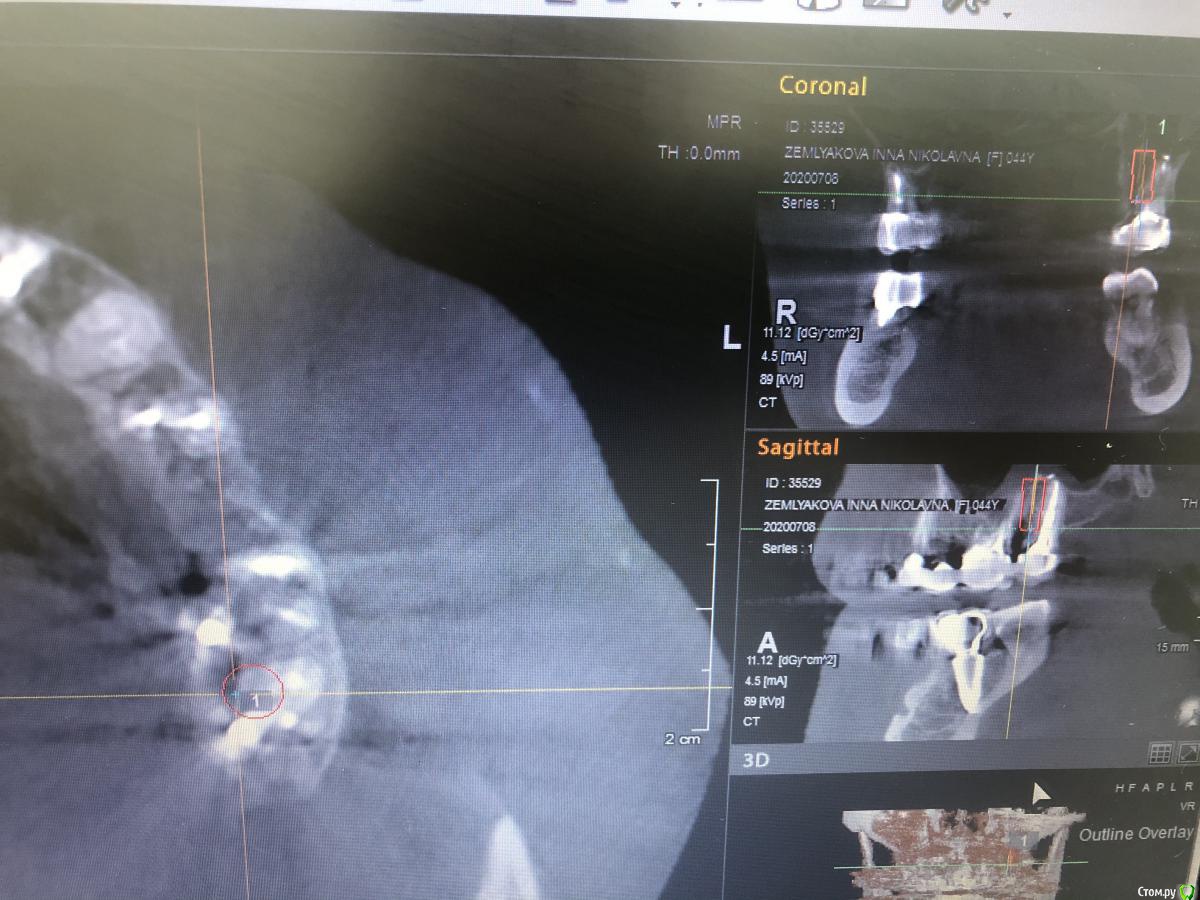

Александр07 Опубликовано 1 июля, 2020 Поделиться Опубликовано 1 июля, 2020 Коллеги доброго дня, пац 55-60 лет, хочет чтобы было красиво и крепко держалось, такая ситуация во рту, планируем операцию на вчКак видите примерно в обл 1.4-1.6 дефект по высоте, размышляю по поводу установки 1.1,1.3, 2.2,2.4 с расщеплением в обл 1.3, под протез на балке, Врем конструкция на импл , даже при условии что получится без большой подсадки, не рискнул бы- крупный мужчина, будет давать нагрузку, если ставить Мини импл то планировал бы позиции 2.1,2.5, 1 сегмент пока не ясно куда ставить ) По аугментации в обл 1.5-1.6, что посоветуете- делать /не делать, одновременно с фронтом или отдельно, или ограничиться тем планом по балке что написал выше , В обл 2.5-2.6 синус нужен trim.F286E467-8CC6-421B-ACE6-47434003E04E.MOV Ссылка на комментарий

Александр07 Опубликовано 14 августа, 2020 Автор Поделиться Опубликовано 14 августа, 2020 Коллеги планируется имплантация на вч-удаление 2.4,2.6, 2.7 под ? ( ферула нет после снятие мк, можно попробовать удлинить но ортопед не особо настроен ) , здесь сложность в том что пац не может ходить без зубов, чтобы окружающие не знали об этом, Первый вариант это удаление 2.4-2.6 и капа , второй вариант это убрать 2.4,26.2,7 и импл с нагрузкой 2.4,2.5, 2.7 Вот срезы, скажите что думаете , насколько вероятно нагрузить и стоит ли, в обл 2.5 по хорошему откр с лифт, можно попробовать закрытый, 2.7 придётся смещать к перегородке межзубной Ссылка на комментарий